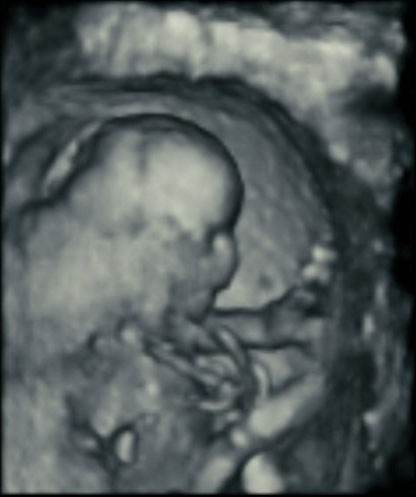

Here’s how ultrasound works in pregnancy: As early as 16 weeks, women can see a “fetal portrait” of their baby and determine its gender. Ultrasound technology has improved dramatically over the decades from flat, grainy black and white images to the current three-dimensional time experience.

Most hospitals offer some 3D scanning, but 3D ultrasound produces images that show the width, height and depth of a developing child. Rather than sending sound waves straight into the womb and recording when they bounce back as is common in 2D imaging, 3D ultrasound sends sound waves from different angles. A computer then renders a 3D image based on this data.

4D ultrasound adds movement as it occurs. The fourth dimension is time. You’re actually watching your baby live in 3D mode. How cool is that?